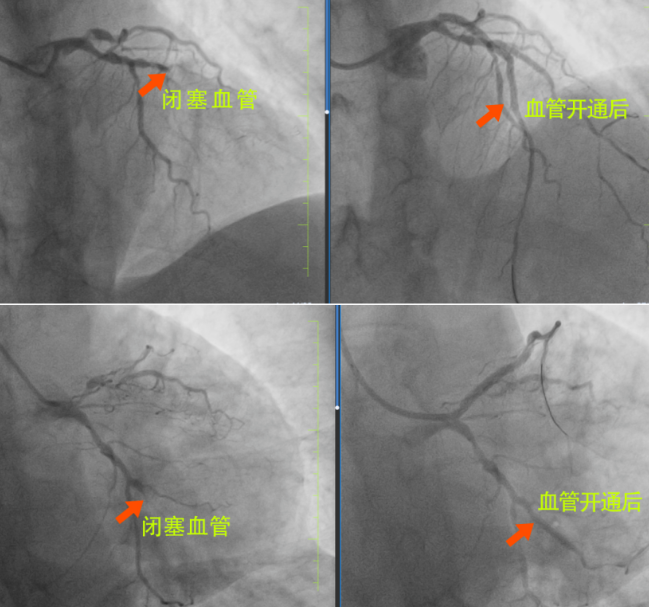

很快,長春國文醫(yī)院心內科為患者安排了手術,為患者進行手術的是長春國文醫(yī)院副院長、心血管中心主任隋立有。隋院長在心血管領域造詣深厚,擁有豐富的臨床經驗。隋院長始終專注于心血管疾病的研究與治療,對各類復雜心血管病例有著獨到的見解和精準的判斷。隋院長在了解患者的病情后,迅速制定了治療方案?;颊?根血管完全閉塞,情況十分危急。但隋院長憑借著精湛的醫(yī)術和豐富的經驗,巧妙地開通了2根血管,整個手術過程僅僅用了不到半小時,就成功完成了3枚支架的植入。這一高效且精準的手術,讓患者和家屬驚嘆不已,也讓他們真切地感受到了國文醫(yī)院心內科雄厚的師資力量和成熟的技術實力。